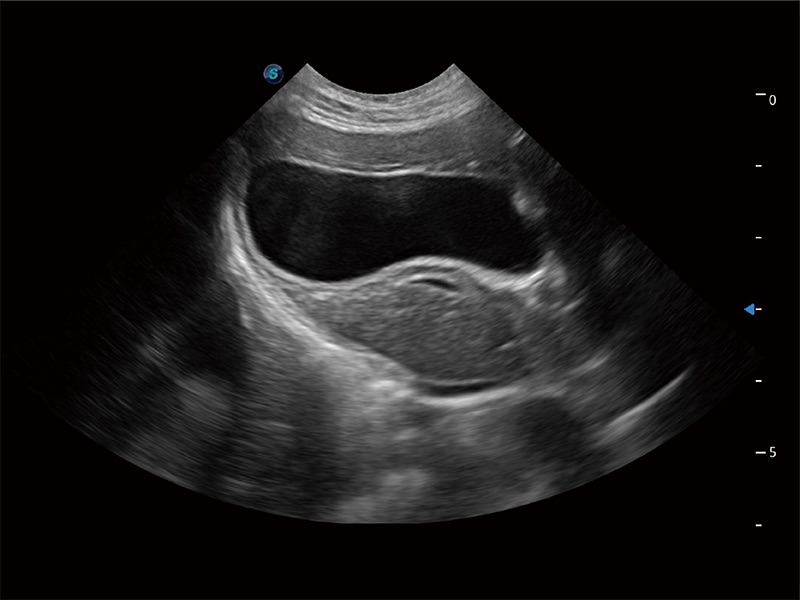

高性能和先进的临床应用工具可以为动物医生提供临床信心。ProPet 80 搭载了先进的腹部和浅表应用工具,帮助医生在日常临床实践中发挥前所未有的作用。

极大提升超低速微细血流的检出能力,同时更精准地滤除软组织和超声信号,为兽用医生提供以往无法通过常规血流获得的疾病诊断信息。

ProPet 80 专为动物医生设计,对不同的动物体型和生理结构作出了针对性的优化。通过动物影像专用软件,可满足个性化的应用需求,帮助动物医生获得更精确的诊断数据。

ProPet 80 全新的动物超声智能软件和丰富的探头群,为动物医生提供了高清晰度和精细分辨率的图像,无论在宠物、马科、畜牧还是实验室动物等应用中都可以轻松应对,为您的日常工作带来满意的体验。